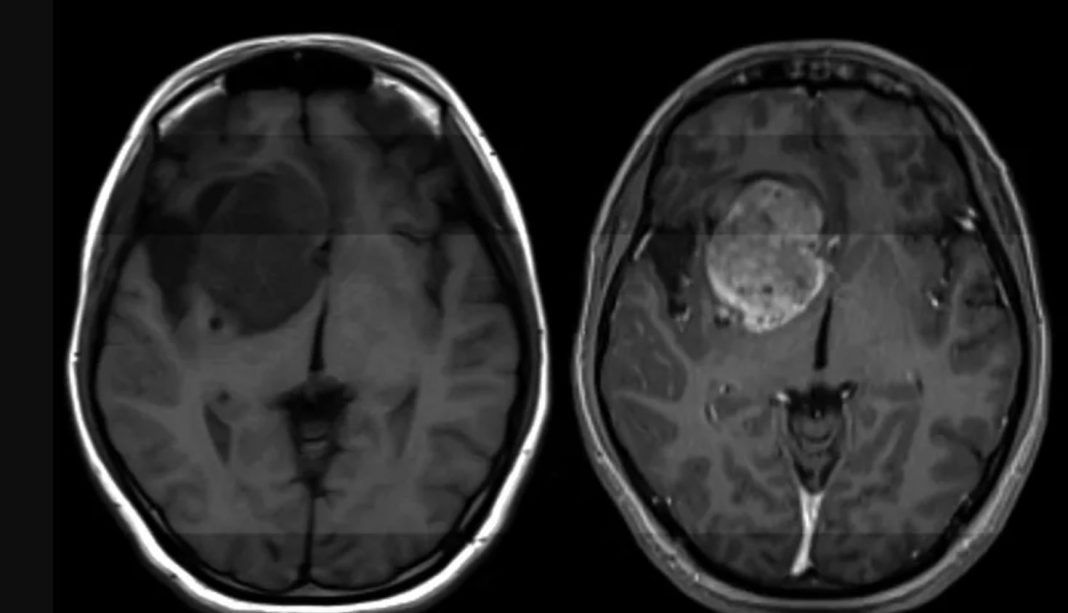

Ας μια άκρως πολύ σημαντική εξέλιξη όσον αφορά την παθολογία του γλιοβλαστώματος, ένας από τους πιο συχνούς καρκίνους του εγκεφάλου για τον οποίο αυτή τη στιγμή δεν υπάρχει κάποιου είδους θεραπεία. Ερευνητές σε επιστημονική δημοσίευσή τους στο Science Translational Medicine, αναφέρουν ότι κατάφεραν να βρουν τρόπο να τον καταπολεμήσουν.

Σύμφωνα με στοιχεία, κάθε χρόνο περισσότεροι από 14.000 άνθρωποι στις ΗΠΑ διαγιγνώσκονται με γλοιοβλάστωμα, ένας επιθετικός, απρόβλεπτος και χωρίς δυνατότητα πρόληψης καρκίνος στον εγκέφαλο.

Καθένας από αυτούς τους νέους ασθενείς στους οποίους γίνεται διάγνωση του εν λόγω καρκίνου θα ζήσει κατά μέσο όρο για 12 με 18 μήνες χωρίς να υπάρχει κάποια θεραπεία και μόλις μία στις 20 περιπτώσεις θα καταφέρει να παραμείνει εν ζωή μετά από 5 έτη.